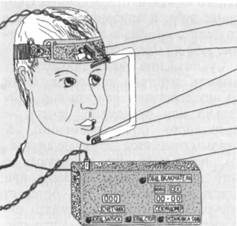

Регистрация движения нижней челюсти — гнатография проводится по методу Рубинова. Получаемые с помощью прибора мастика-циограммы позволяют судить о характере движения нижней челюсти во время функции жевания (рис. 13.34). Для подсчета жевательных движений при проведении функциональных проб используют метод Персина (рис. 13.35).

Рис. 13.34. Мастика-циограф и мастикацио-граммы.

Рис. 13.35. Устройство для подсчета количества жевательных движений нижней челюсти.

1 — фиксирующее устройство; 2 — шарнир; 3 — магнит; 4 — рама; 5 — датчик герконо-вый; 6 — прибор для подсчета нижней челюсти во времени.